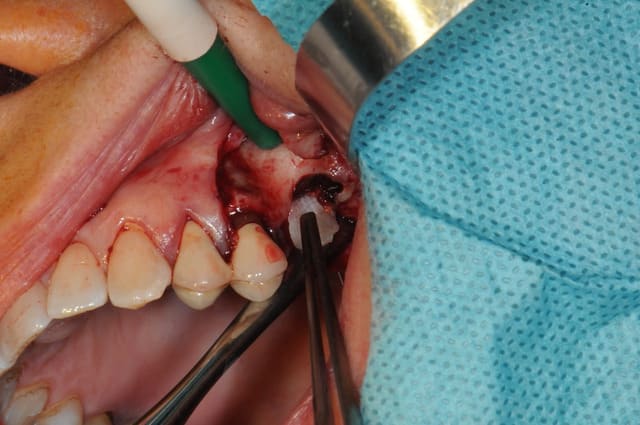

je fais bref!

déjà ne fais pas la même chose que moi; décales ton trait d'incision par rapport à l'entrée de la CBS

- coupes la communication entre la membrane de Schneider et la muqueuse (ici, c'était à moitié de la gencive et de la boule de Bichat mélangée avec du tissus de granulation)

- cautérise avec un bistouri électrique ou un simple bistouri chauffé à blanc.

- refoules le sinus

- prf

- combles (Rog +membrane, ...)

-sutures et le tour est joué.

fais nous des photos, les miennes sont pourries, les piles étaient nazes...

bonne chir, je t'envie.!!